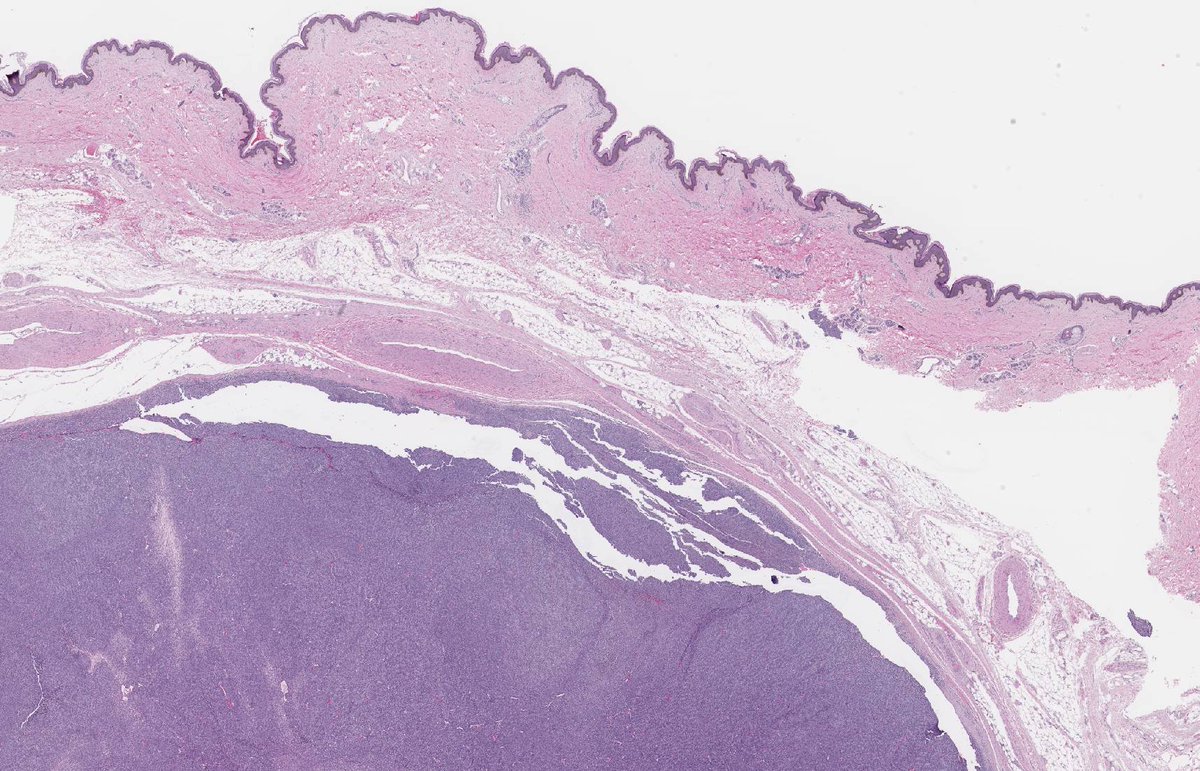

KAPOSI SARCOMA: IHC: HHV8. NB: ectatic, irregularly shaped, thin-walled vessels; collagen dissection; so-called 'promontory sign'; attenuated endothelial cells with eosinophilic cytoplasm; hyperchromatic nuclei showing mild atypia and inconspicuous mitotic activity.

2

28

69